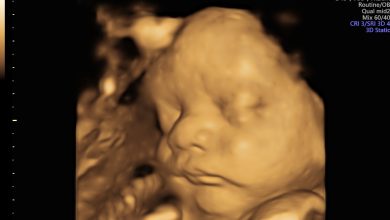

Жаңа туған нәрестелердің ағзасы өте нәзік әрі қорғансыз келеді. 2 айлық баланың тамағы ауырса, бұл ата-ананы қатты уайымға салатын жағдай болуы мүмкін. Мұндай кезде сабыр сақтап, нақты әрекет ету маңызды. Баланың жалпы жағдайын бақылау мен дер кезінде дәрігерге қарату — басты қағидалар.